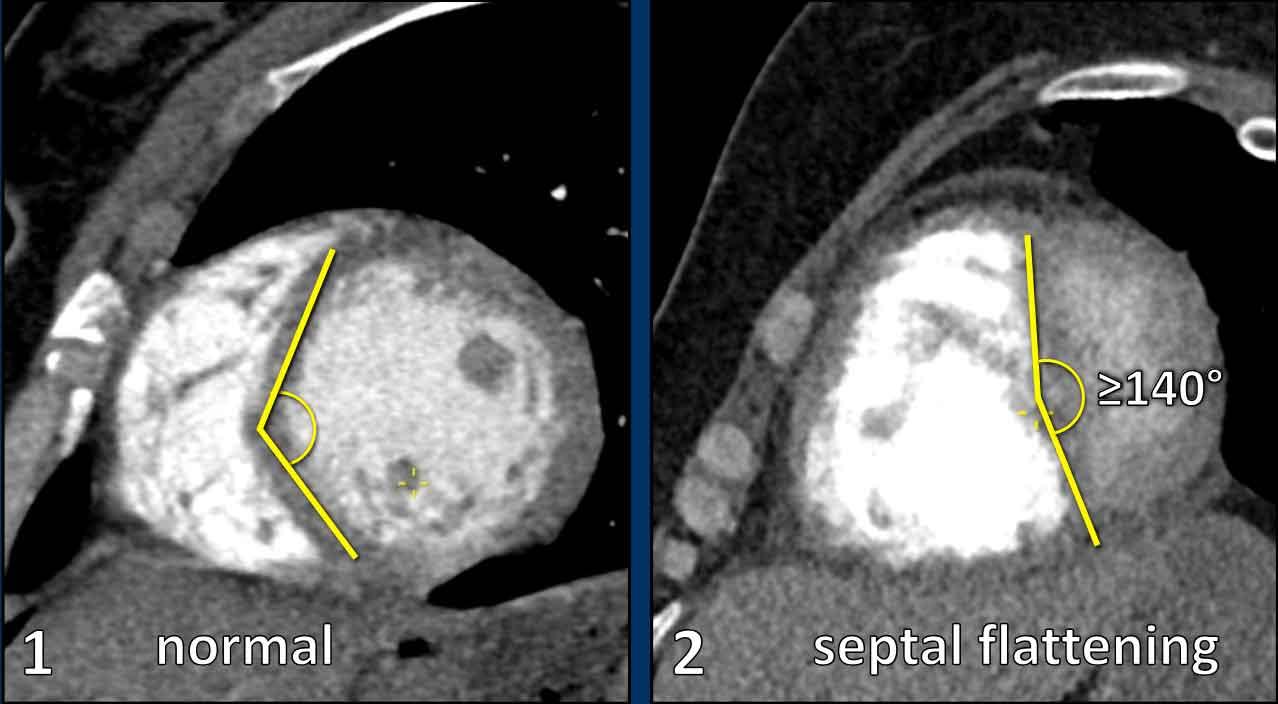

Tỷ lệ TP/TT >1 trên các lát cắt ngang. - Vách liên thất phẳng hoặc vồng sang trái

Trên mặt cắt trục ngắn, thất trái bình thường có hình dạng tròn đến bầu dục.

Vách liên thất góp phần tạo nên đường viền tròn của thành tâm thất.

Vách liên thất bị dẹt hoặc vồng sang trái là dấu hiệu chỉ điểm quá tải áp lực và giãn thất phải.